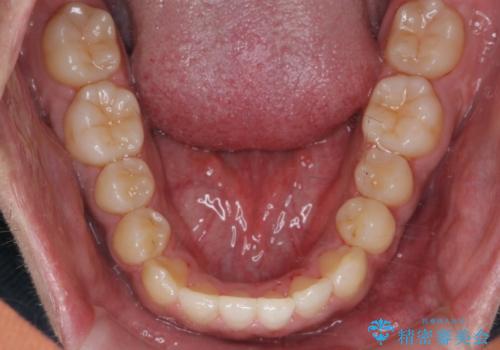

- 受け口を主訴に来院。

前歯のかみ合わせが逆になり上の前歯が奥に入っていました。

骨格性の受け口だったため、矯正用のミニスクリューを用いて、下の前歯をしっかり内側に入れました。

また、下顎はミニスクリューからマウスピースにゴムをかけて、下の歯並びが前に出ないようにして並べています。